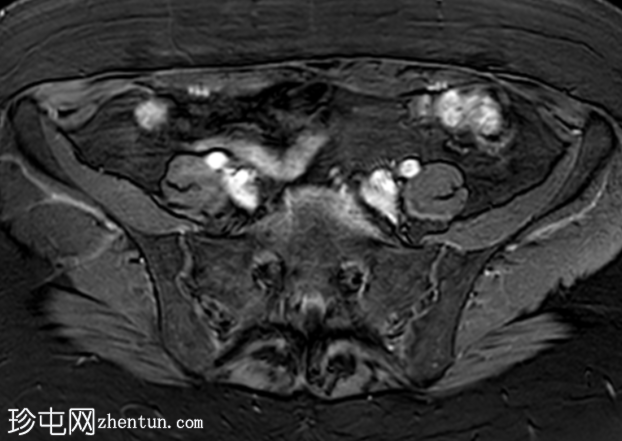

冠状位

T2加权像

盆腔MRI显示左侧骶前区有两个小囊性病变,位于左侧附件的预期解剖位置。

病变在T2加权像上呈高信号,边界清晰,囊壁轻度增厚,光滑。在T1加权脂肪抑制像上,一个病变内部呈高信号,另一个病变呈低信号。静脉注射对比剂后,可见轻度周边囊壁强化,未见强化的实性成分。

未见扩散受限。病灶与邻近盆腔血管关系密切,无周围炎症改变、盆腔淋巴结肿大或游离液体的证据。